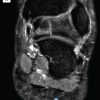

A 24 year old female presented in outdoor patient department with complaints of pain in the left knee of 1 month’s duration. Pain was insidious in onset and increased gradually over a period of 1 month. There was no swelling over the knee joint. There was no history of any significant trauma, fever, cough and night sweats. On clinical examination there was localized tenderness over the tibia just below the joint line. There was no evidence of joint effusion. Passive and active range of motion was within normal limits. There was no evidence of synovial hypertrophy. McMurray’s and Drawer test were negative. An X-ray [Fig. 1&2] of the knee joints (AP and lateral) showed a lytic lesion in the centre of the right tibia in the epiphysis just below the joint line measuring 2*1.5 cm. It was well defined lesion with well defined border and narrow zone of transition. Other bones being normal. MR imaging was suggestive of brodie’s abscess [Fig.3]. Differential diagnosis–brodie’s abscess, tuberculosis, Giant Cell Tumor, Chondroblastoma, Langerhans Cell Histiocytosis, Metastases, Aneurysmal bone cyst, Osseous Lipoma, Osteomyelitis, Subchondral Cyst. Fine needle aspiration cytology was inconclusive. Total leukocyte count was 9400/cmm with 60% of neutrophils and 35% of lymphocyte. ESR was 25 mm by Wintrobe’s method. Since MRI was suggestive of Brodie’s abscess, so needle biopsy or true cut biopsy was not done. Treatment: Since aspiration cytology was inconclusive and MR was suggestive of brodie’s abscess so our treatment was to drain the abscess cavity and fill the cavity with bone graft substitutes. Intra-operatively there was thick sclerotic wall but there was no pus formation. There was soft tissue accumulation which had a yellowish tinge and cavity was found. Tissue was sent for histopathology and culture sensitivity. The cavity was filled with bone graft substitutes. Routine antibiotics were given post-operatively with Gram positive and Gram negative coverage. Histopathology[Fig.4&5]: Report was suggestive of malakoplakia and there was no growth on culture. Histopathology shows sheets of histiocytes and plasma cells in the bone.CD markers study showed positive for CD 68 and negative for CD 138, CD 38 and light chains (kappa and lambda)[3]. Michaelis and Gutman bodies were not seen. Our case was in stage 1 of malakoplakia also called as `early prediagnostic` phase in which there is infiltration with plasma cells and macrophages with absent michaelis and gutman bodies [13].